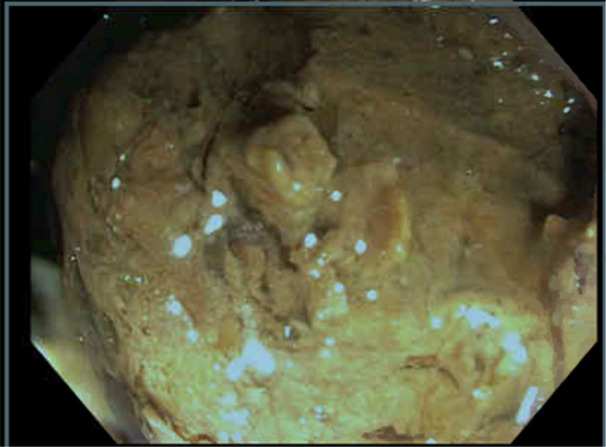

Gastric bezoars and small bowel bezoars are uncommon in the pediatric population, and colonic bezoars are even rarer. We present the case of a 9-year-old female who presented with acute abdominal obstruction symptoms and a diagnosis of colonic phytobezoar. The phytobezoar was removed via endoscopic intervention. This case is important as it demonstrates that colonic bezoars can occur in children, may not be amenable to oral laxative or enema therapy, and may require endoscopic removal.